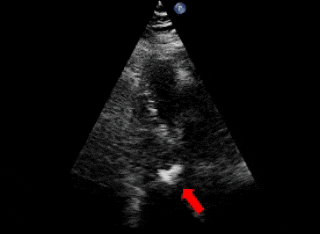

术前超声、造影

主动脉瓣上造影,破口约5mm